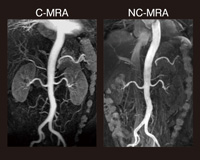

非造影MRAのシーケンスは,(1)Flow Prep法,(2)IFIR(InFlow Inversion Recovery)法,(3)IR-IFIS(In-Flow-Iterative Spatial sat)法の3つが基本となる。Flow Prep法は,目的とする血管の最高血流速度に合わせてRFパルスを印加して目印をつけ,拡張期に撮像することで,動脈を選択的に描出する方法である。図1では,左の造影MRAの腎動脈では静脈が重なり合って評価しづらいが,右の非造影MRAでは末梢まで明瞭に描出されている。

図1

図1 腎腫瘍